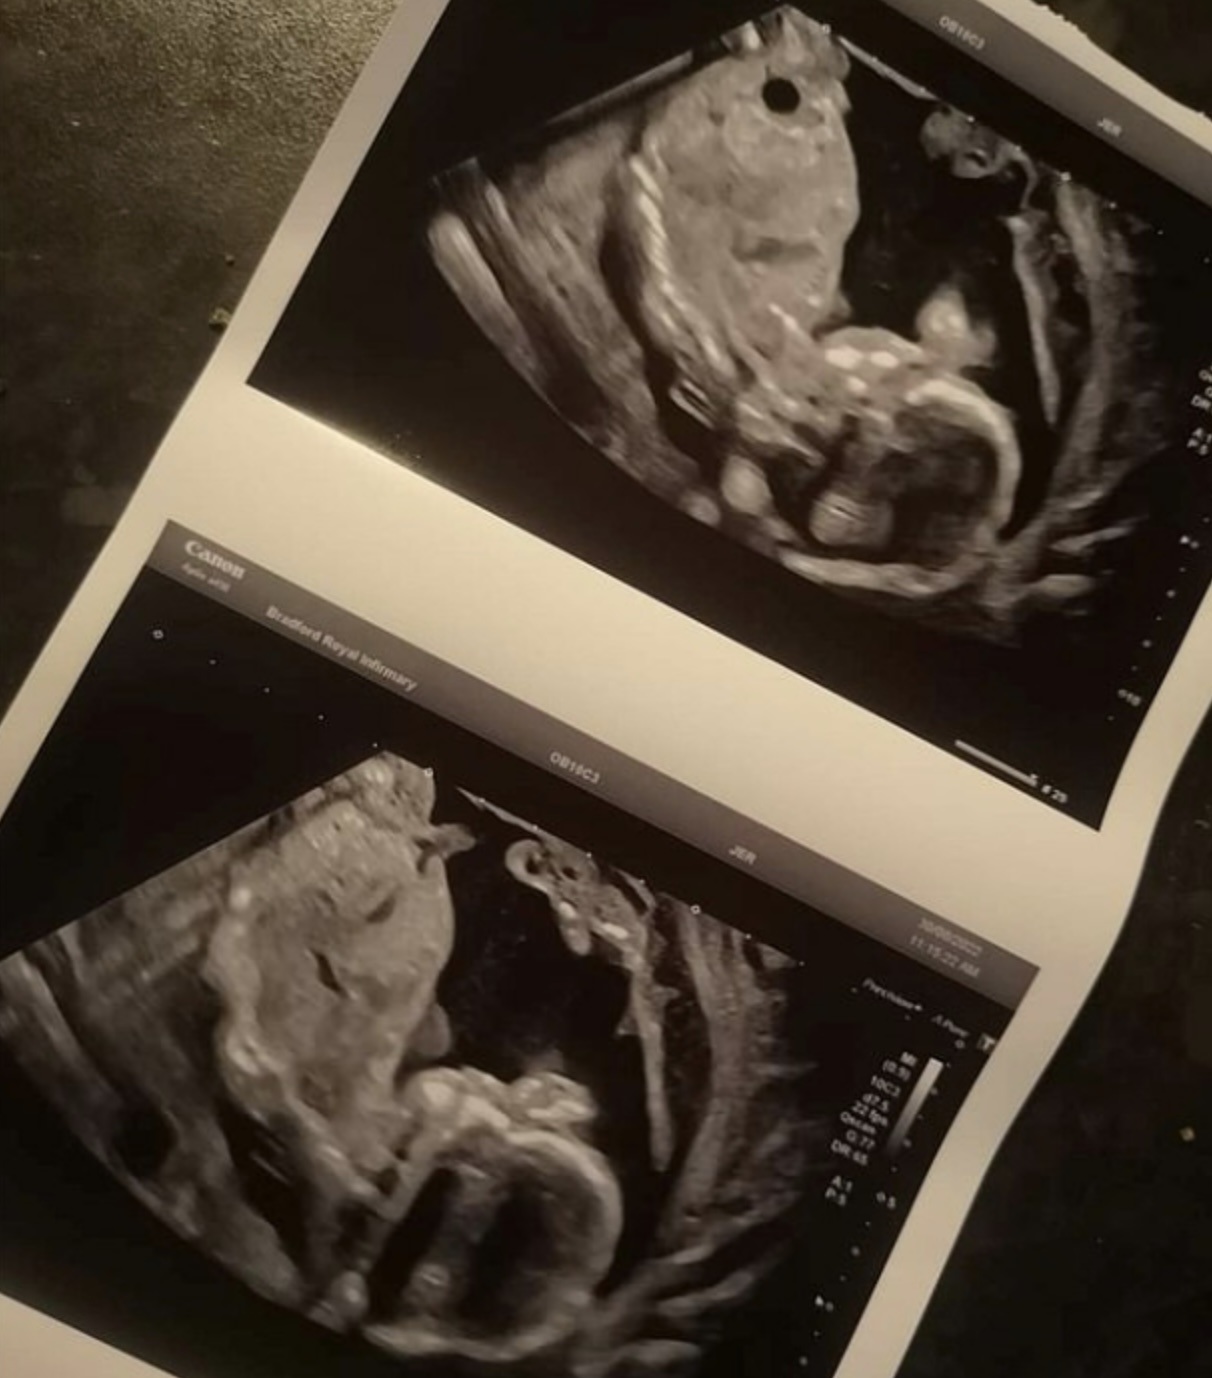

綜合外媒報道,英國一名女子Hannah Cole在懷孕20周時不幸提早穿羊水,被緊急送往Bradford Royal Infirmary醫院。隔日醫生告知她在檢查的過程中,已經檢測不到她腹中寶寶的心跳,因此要為她安排手術引產。這讓Hannah十分難過,難以接受寶寶已經不在事實。

在進行引流手術前,Hannah的腦海突然閃出一個直覺,認為腹中的寶寶還活著。於是她便要求醫院在手術前為她再進行一次檢查。沒想到,就在這「最後一次」的檢查中,竟發現嬰兒真的尚存心跳!

4周後,Hannah順利誕下一名男寶寶Oakley Cole-Fowler。但由於寶寶是早產嬰,體重僅有780公克,且患有壞死性小腸結腸炎。所幸接受手術後,寶寶的復原狀況相當好,目前已經可以不用繼續使用呼吸器。